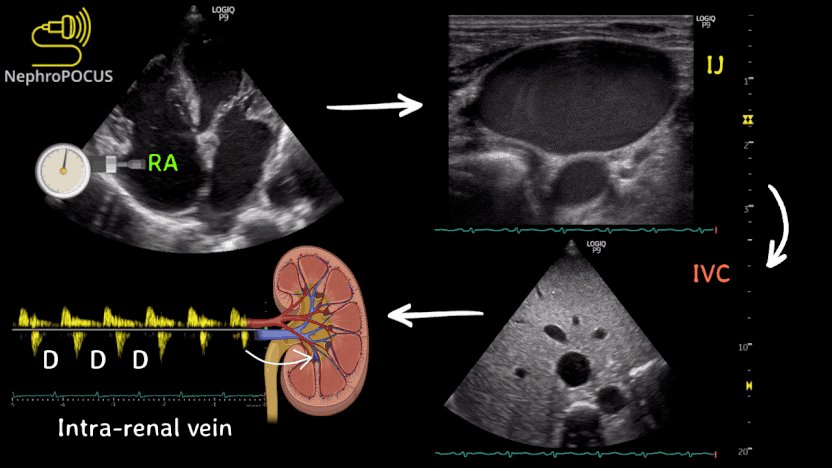

(4/x) Venous congestion is a pathologic state where high venous pressures are transmitted retrograde from the right atria into organs like the liver, brain, kidney, and bowel causing organ dysfunction.

CVP predicts venous congestion, but only weakly.

#VEXUS or #Doppler markers of congestion are better predictors of venous congestion.

IVC certainly has some role in this too - for patients with a totally collapsed IVC, they are less like to have venous congestion. For patients with a severely distended IVC, they are more likely.

This however, (like CVP) is actually imprecise at a patient level with only moderate predictive accuracy, which is why #VEXUS uses organ level Doppler of the hepatic vein, portal vein, and intra-renal vein to predict fluid responsiveness

Credit to @NephroP for this great diagram and if you want to learn more about congestion, nephropocus.com is probably the best resource out there!!!